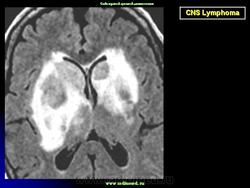

Локализируется в основном в больших полушариях. Некоторые больные могут иметь лимфому в других частях тела. В головном мозгу, не редко, могут иметь место множественные локализации. Диагноз подозревается на основе изображений КТ и МРТ.

Диагноз подозревается на основе изображений КТ и МРТ.